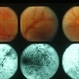

- Cryptococcus

- cryptococcus, meningitis

- 60-year-old male, III cryptococcus meningitis, 20/32 OU (AIDS).